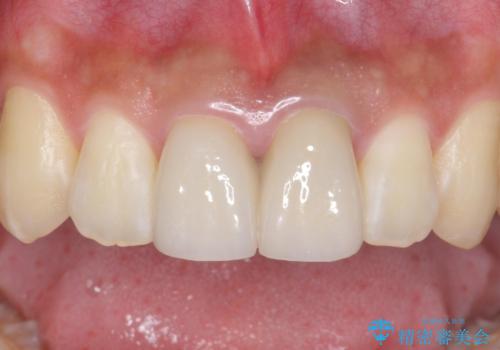

歯のガタつきも解消することができました。

e-maxクラウンでは仮着ができませんが、今回は一回でご満足いただける修復ができました。